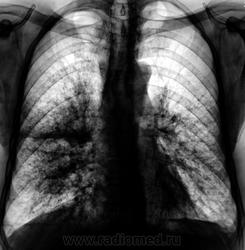

Вот и контроль после лечения подоспел...

Динамики нет... К онкологам пойдет?

А клиника после лечения как? Визуально-то - не "айс". Мягко говоря - без динамики.

Жалоб нет, температуры нет, только кашель с мокротой. Мокрота со слов пациента и жены его светлая, без примесей.